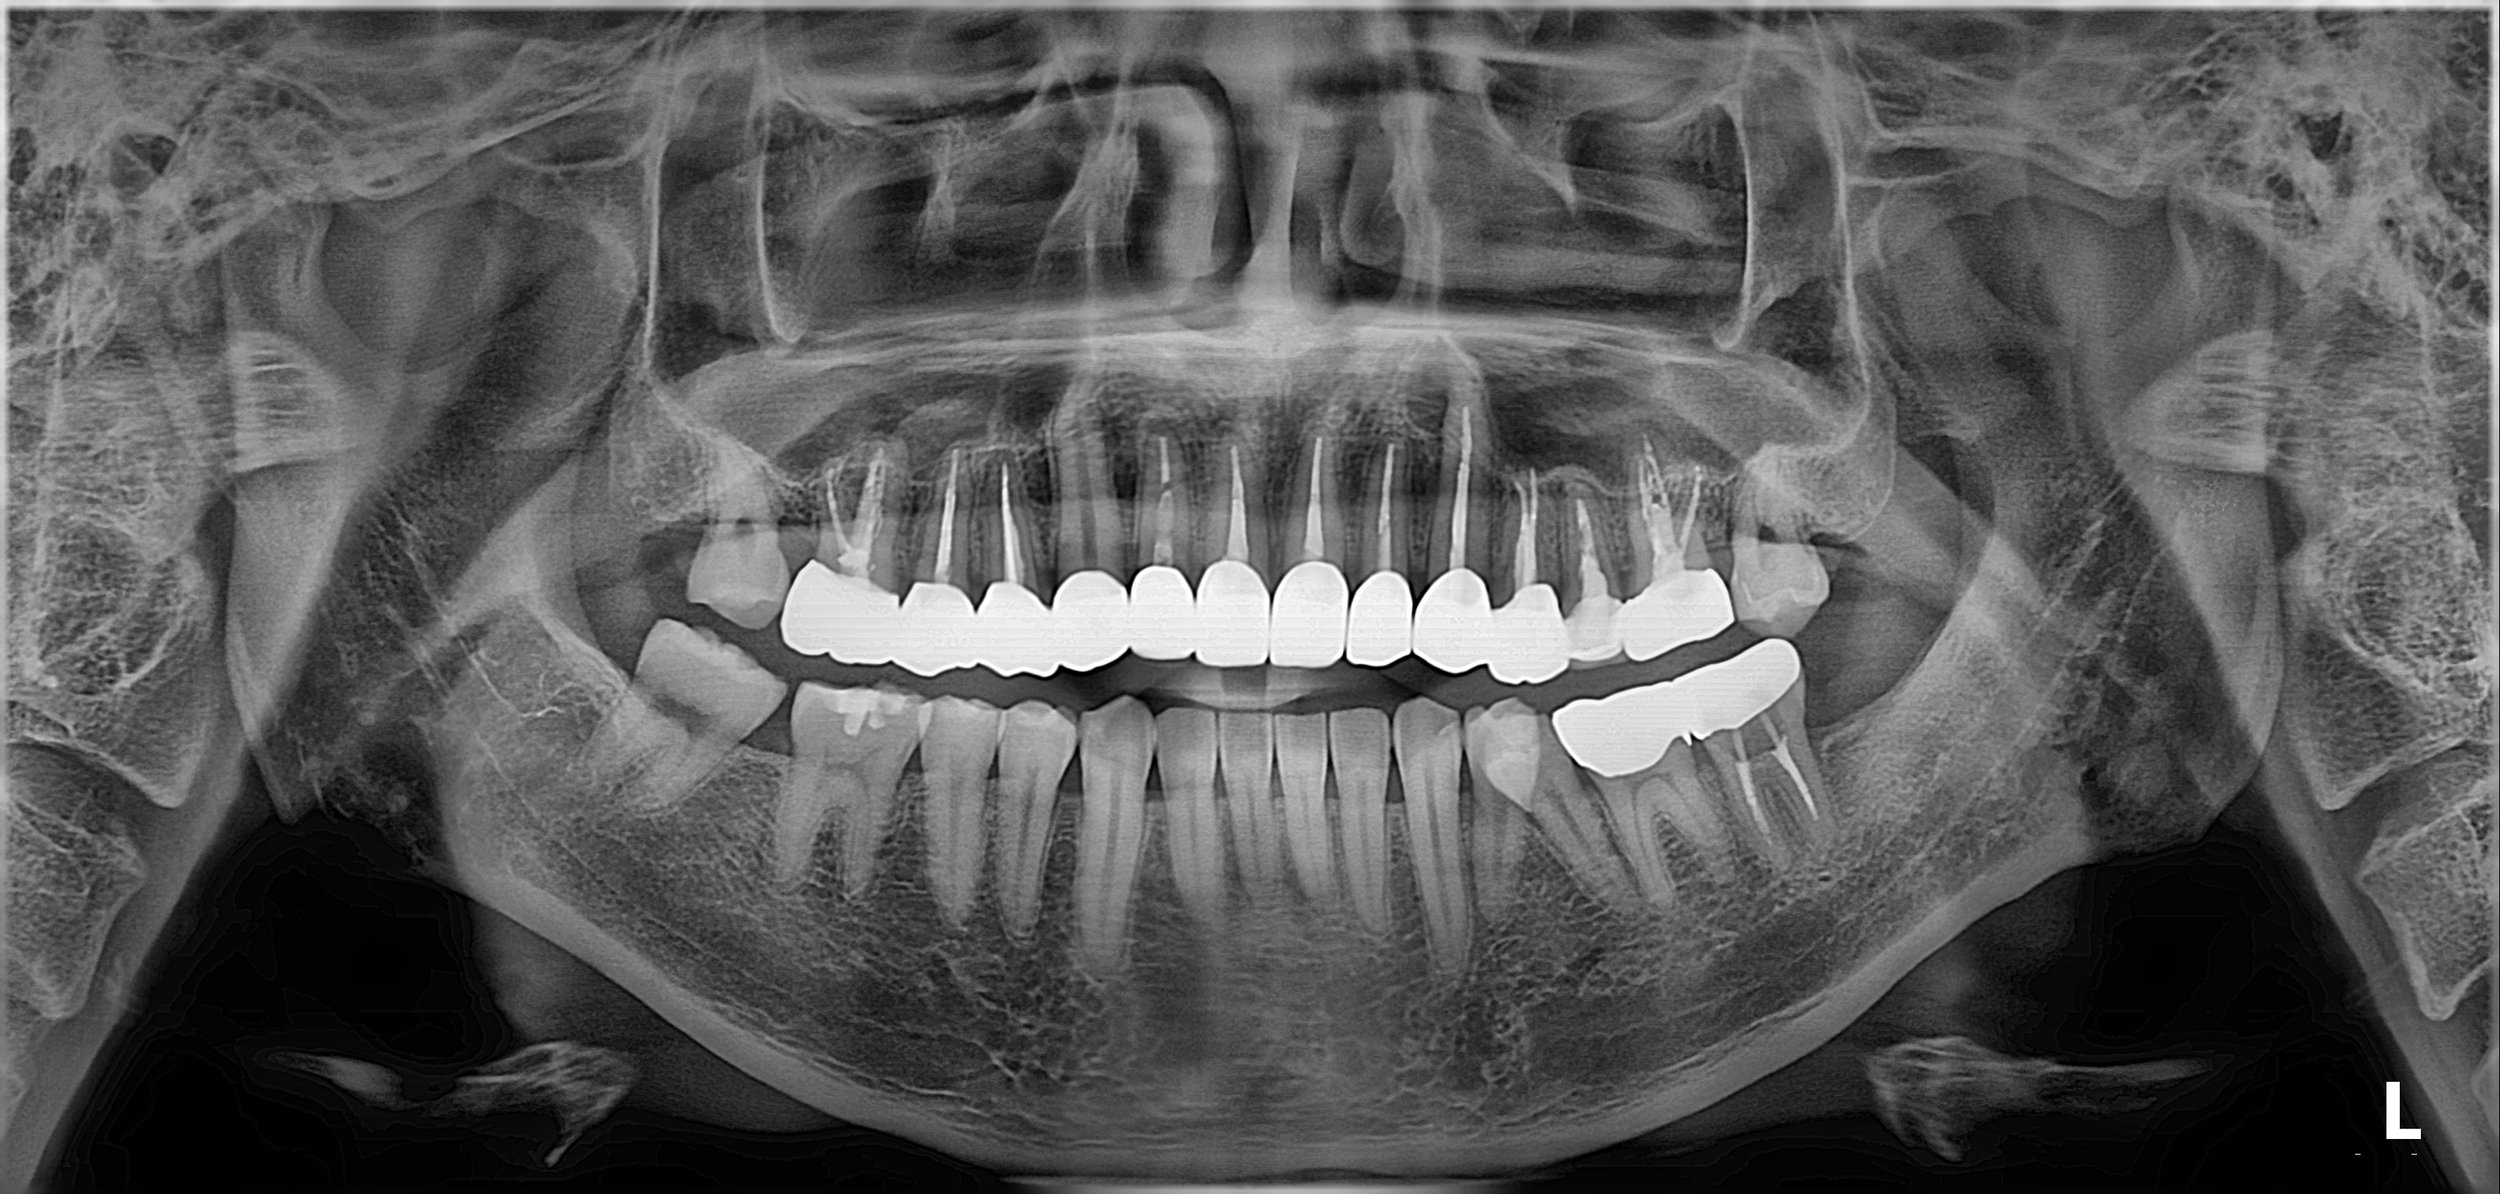

INTRA ORAL - AFTER

2. Occlusal Reset: A thorough diagnostic wax-up was used to determine the ideal midline and occlusal plane. The goal was to compensate for the mandibular deviation by repositioning the dental midline during the prosthetic phase.

3. Prosthetic Rehabilitation: All-ceramic crowns were utilized to restore the severely decayed teeth. By meticulously adjusting the morphology of the final crowns, we were able to successfully harmonize the upper and lower midlines and correct the perceived facial asymmetry.

4. Functional Harmony: The final occlusion was calibrated to ensure even distribution of forces, providing the patient with a stable bite that resolved the functional discomfort associated with his previous deviation.

The result is a transformative improvement in both oral health and facial aesthetics, giving a young patient a confident and functional smile for the future.